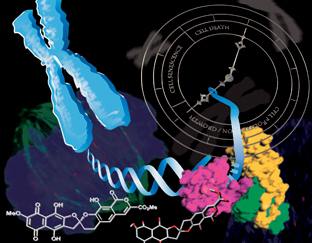

Chasing a cancer suspect to cytokinesis

A potential new way to target aggressive cancers has been identified through a MWC project as part of the research programme investigating genomic approaches to cancer diagnosis an

One cancer gene – but several different proteins

Cancer arises due to changes in DNA in a single cell. Many changes are needed over time to a cell’s DNA to make it cancerous – which is why cancer is usually a disease of later li

Turning the tables on cancer

Tumours often contain areas with less oxygen than is found in normal tissues. These areas are less vulnerable to many forms of cancer therapy and often drive development of a more

read the full story

The tumour-promoting activities of a famous protein

Developing new cancer therapies and a more reliable test for prostate cancer are just some of the potential outcomes of Maurice Wilkins Centre research into the cellular mechanisms